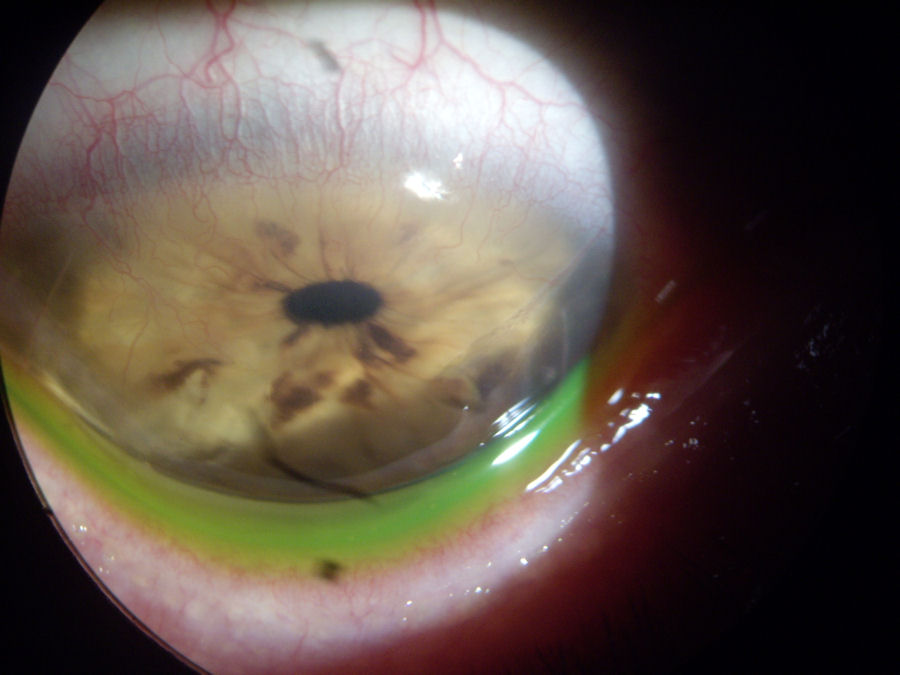

На четырех изображениях ниже представлены фотографии и сканы правого глаза пациента, перенесшего два рк хирургических вмешательств и двух операций LASIK, а впоследствии разработанных эктазия , неоваскуляризация и стафилококковая инфекция. (Все четыре изображения можно увеличить, щелкнув на изображении.) На верхнем левом снимке красная стрелка указывает на лоскут LASIK, который никогда полностью не заживет. Две черные стрелки указывают на открытые разрезы, через которые кровеносные сосуды проникают в роговицу (неоваскуляризация). Это создает угрозу зрению. Глаз покраснел и налился кровью в результате стафилококковой инфекции. Следующие 3 изображения представляют собой сканы роговицы в поперечном сечении, на которых видны повреждения от разрезов и истончение, связанные с эктазией. Этот случай демонстрирует эффект домино от ненужной операции на глазу .